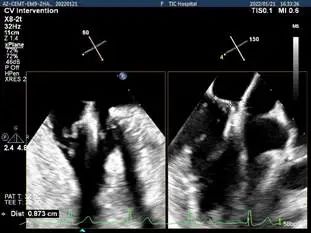

TEE Bicom view:二尖瓣后叶P2区脱垂,宽16.3mm

Color-view:大量反流,主要血流PISA来源于2区

穿刺点高度测量:4.39cm

3D视图菲薄的卵圆窝,穿刺点位于房间隔中部略靠前,3点略偏2点位